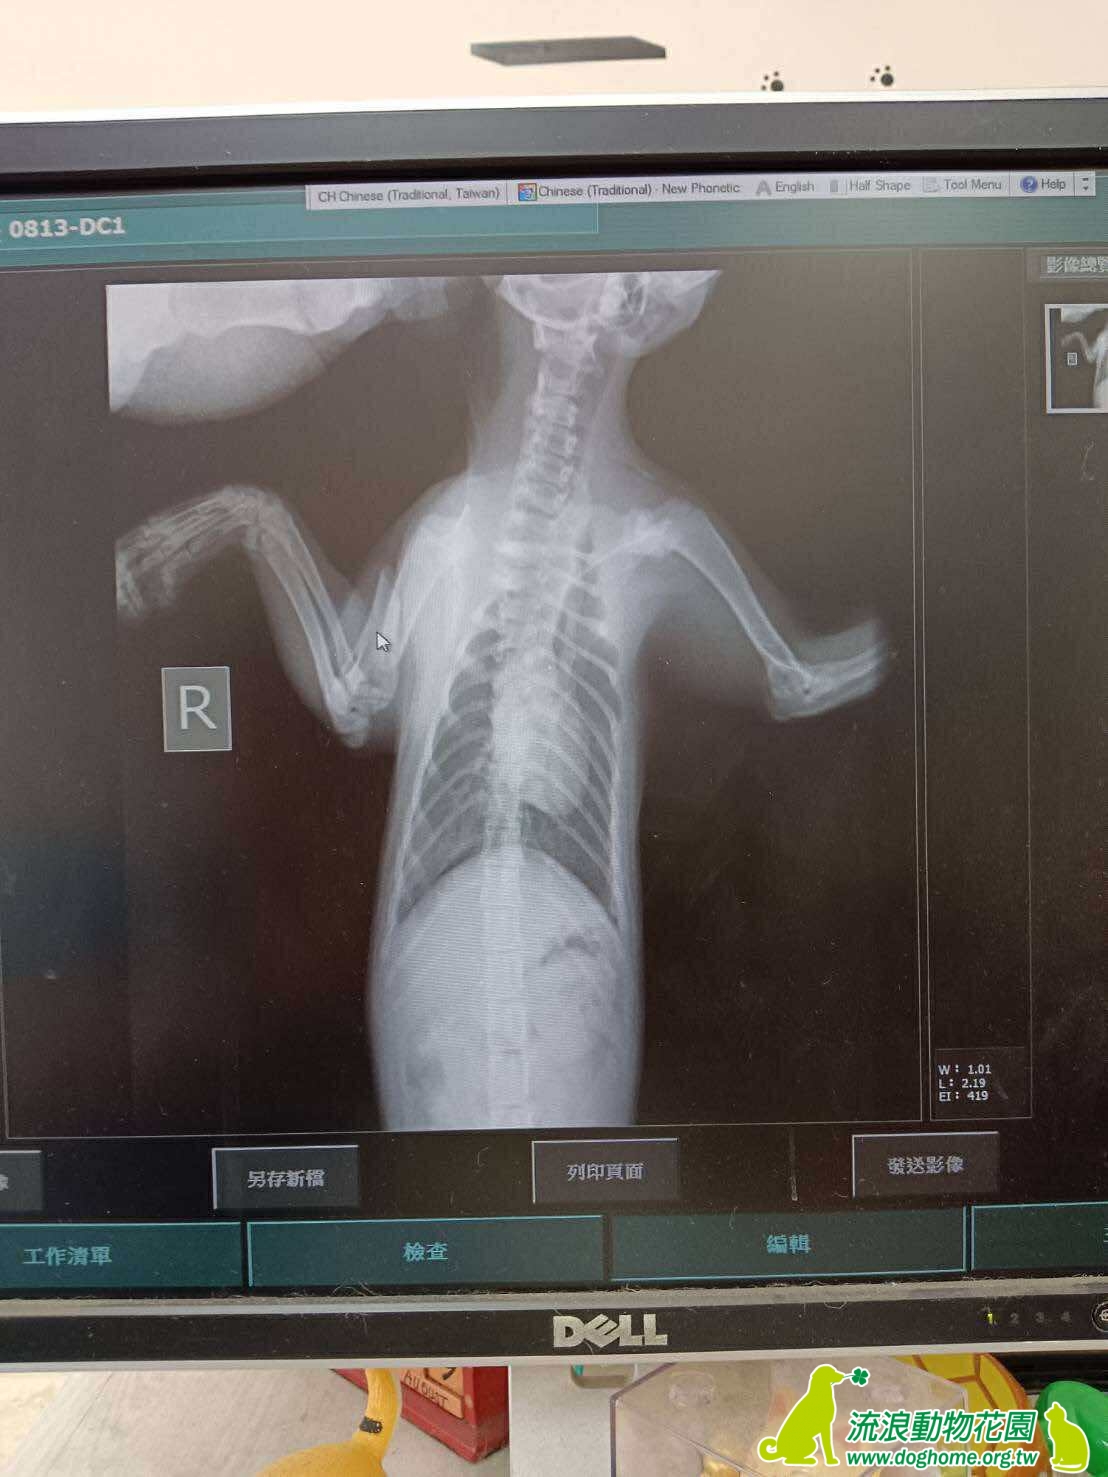

小截進所時的傷比較嚴重,獸醫判斷已經傷到神經

所以直接截去了一隻腳

牠沒有健全的四肢,但需要你來看見!小截是一隻名副其實的三腳貓,來自南投收容所,入所前不知道發生什麼可怕的事故,經獸醫評估後截去右前腳,固然行動不便,走路一跛一跛,但還是能像一般貓來去自如,跳上跳下。

牠可摸可嚕可抱,非常的親人,撒嬌是牠的專長,抱抱可以待在身上很久,題外話,還有一個突發技能,自行拆線(回診截肢狀況時習得XD),剛帶回家可能會覺得牠是一隻I貓,不太活潑,可能是過去歷經入所收容、截肢,獨自關籠靜養,加上感冒,脫離了群體生活,但其實牠個性溫順,加上也還在習慣三腳生活,不用太過擔心,牠的飼養照顧如同普通貓咪一樣,唯一可能比較需要注意的是體重上的維持,避免另一隻前腳負荷太大。